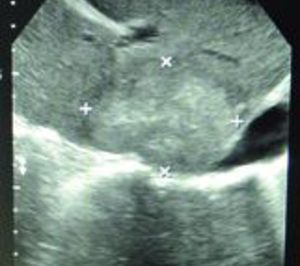

El grupo hospitalario madrileño HM Hospitales acaba de incorporar a su cartera de servicios la nueva técnica de electroporación irreversible para el tratamiento de tumores hepáticos y pancreáticos. Se trata de una técnica que utiliza energía no térmica para lograr la ablación de tumores, permitiendo preservar estructuras vitales dentro de la zona ablacionada. Esta técnica, que representa un notable progreso en el tratamiento del cáncer y que está disponible en un número muy reducido de hospitales en todo el mundo, se ha utilizado ya para tratar a tres pacientes en el centro hospitalario HM Universitario Sanchinarro (HMS) desde el pasado mes de julio.